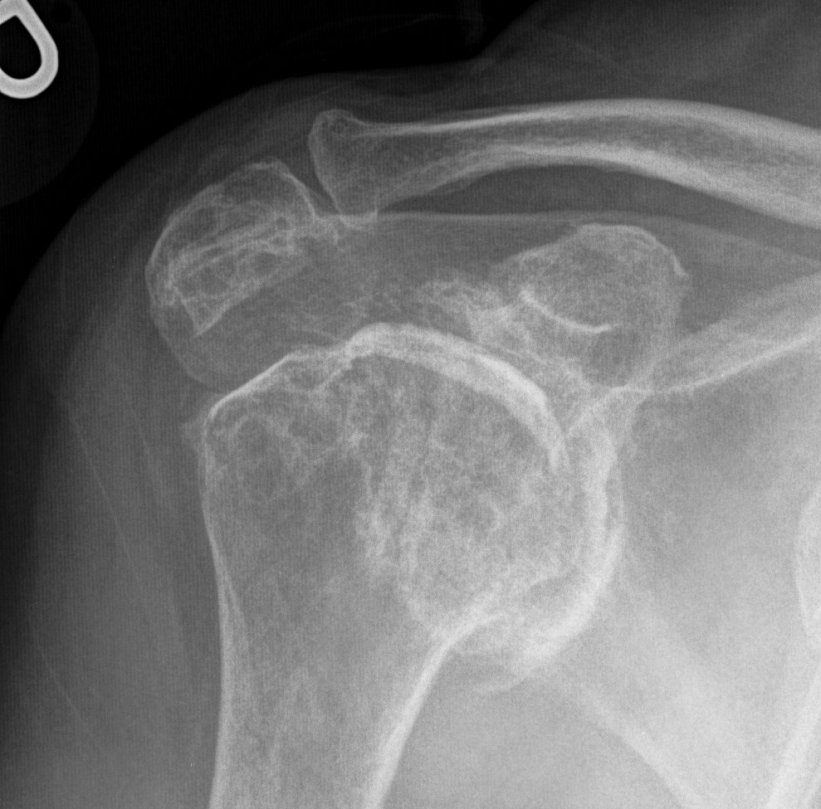

Rheumatoid arthritis with superior and medial wear

Glenoid deficiency

Levigne and Franceschi Classification

Three main patterns

| Type 1 | Type 2 | Type 3 |

|---|---|---|

|

Upward migration Superior glenoid wear |

Concentric medial migration Deficient medial bone stock |

Destructive |

Due to rotator cuff insufficiency Most common pattern |